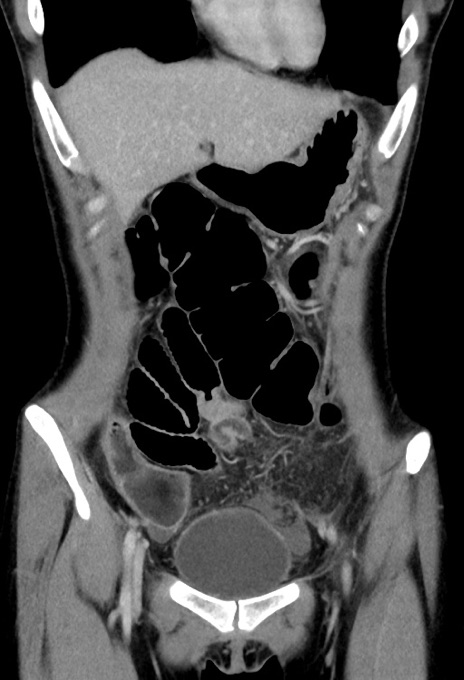

症例17(冠状断像)

【症例】20歳代女性

【主訴】嘔吐、下腹部痛

【現病歴】昨日夕食後に嘔吐し下腹部痛が出現。本日になっても嘔吐持続し改善しないため来院。

【身体所見】意識清明、BT 37.2℃、BP 108/67mmHg、腹部:平坦、やや硬、下腹部正中から右にかけて圧痛あり、反跳痛軽度あり、tapping pain(+)。

【データ】WBC 13600、CRP 14.94